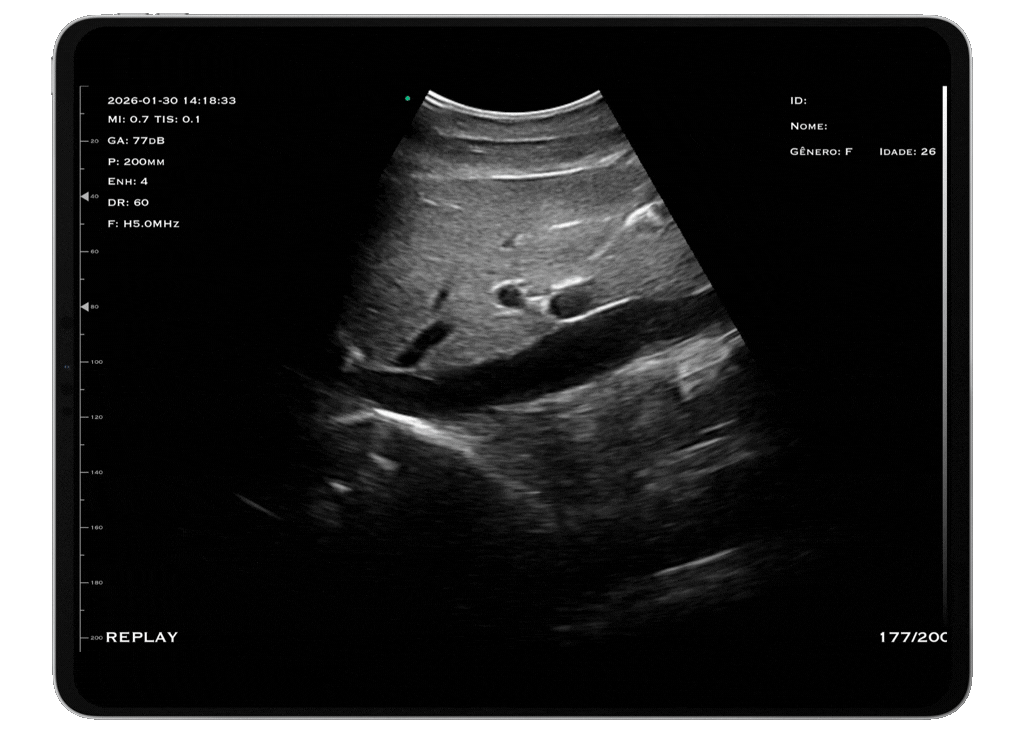

Com tecnologia convexa e frequência de 3,5 a 5 MHz, o modelo M3HD é a escolha ideal para quem busca excelente penetração e visibilidade em exames abdominais, pélvicos e obstétricos.

Seu transdutor convexo oferece imagens nítidas e detalhadas, permitindo a visualização precisa de órgãos internos, como fígado, rins, útero, ovários e estruturas fetais. A baixa frequência garante maior penetração, ideal para exames que exigem avaliação de estruturas profundas.

Aplicações: Ultrassom abdominal, exames obstétricos e pré-natais, avaliações renais e rápida identificação de lesões.